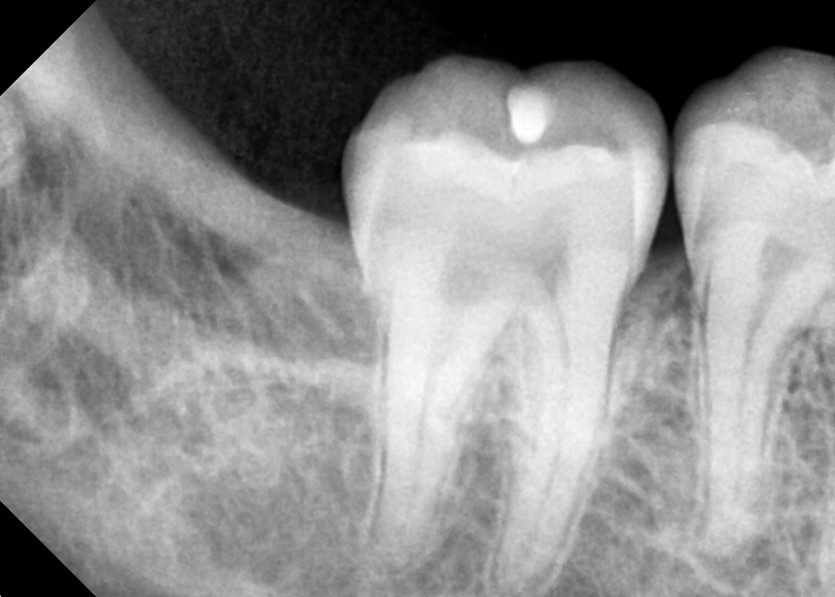

#18,48 사랑니 발치

구강 외과 전문의가 당일 발치했습니다.